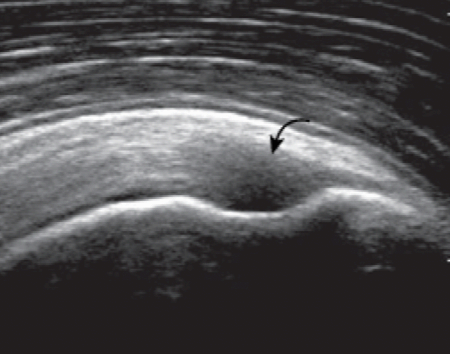

자세 5. 가시위근

가시위근힘줄의 초음파 검사에서 가장 중요한 열쇠는 가시위근(supraspinatus)의 해부학을 이해하고 팔의 위치에 따른 힘줄의 변화를 아는 것이다. 팔을 중립상태로 놓은 자세에서 가시위근힘줄의 긴축영상을 얻기 위해서는 탐촉자를 거친 면위에 관상면을 따라 위치시켜야 한다. 그런데, 이곳에서 가시위근힘줄의 많은 부분은 봉우리뼈 아래에 숨어 있기 때문에 잘 볼 수 없다. 이때 환자의 팔을 안쪽돌림하고, 구부린팔꿉을 몸에 붙인 채로 환자의 손을 환자의 허리 뒤로 옮겨서 바지의 반대편 뒤호주머니에 닿게 하면, 봉우리뼈 밑에 가려진 힘줄이 뼈 밖으로 나타난다. 이자세를 크라스 자세(crass position)라고 한다. 이 자세에서는 위팔뼈머리의 큰 거 친면이 어깨의 앞쪽에 있으므로 탐촉자를 거친 면 위에 세로로 놓으면 가시위근힘줄을 긴축방향에서 검사할 수 있다. 정상 가시위근힘줄은 높은 에코의 섬유다발로 보이고, 위쪽 가장자리가 둥글고 볼록하게 보인다. 관절면 가까이에서 큰 거 친면의 힘줄 붙는 곳에서 힘줄은 아래로 둥글게 구부려지면서(curved downward) 주행하기 때문에 탐촉자의 위치도 그에 따라 각도를 조절하면서 움직여야 하며, 이때 비등방성에 의한 힘줄의 낮은 에코를 병적 소견으로 오인하면 안 된다.

supraspinatus tendon anisotropy 가시위근힘줄이 큰 거 친면에 부착하는 길이는 약 2.25cm 이므로 힘줄의 주행을 따라 탐촉자를 앞뒤로 움직이면서 관찰해야 가시위근힘줄 전체를 검사하는 것이 된다. 또 거 친면의 가장 앞쪽으로 탐촉자를 이동하면서 관절 안 두갈래근 긴 힘줄이 보일 때까지 검사하는 것이 매우 중요하다. 그래야만 가시위근힘줄이 가장 잘 손상되는 앞쪽 끝을 검사할 수 있기 때문이다. 탐촉자를 거 친면의 뒤로 이동함에 따라 위팔뼈머리의 관절면과 거 친면이 만나는 각도가 편평해지고 가시위근힘줄이 깍지 낀 손가락처럼(interdigitating) 보이면서 낮은 에코로 나타나는데, 이는 비등방성 때문이며, 이곳이 가시위근힘줄과 가시아래근힘줄이 만나는 부위이다. 가시위근힘줄을 긴축 방향에서 검사한 다음에 탐촉자를 90도 돌려서 가시위근힘줄을 짧은 축 방향에서 검사한다. 관절 안에서 위팔뼈머리가 볼록하게 높은 에코의 줄(line)로 보이고, 그 바로 바깥을 덮고 있는 관절연골은 낮은 에코로 보인다. 회전근 띠는 아주 가지런한 두께를 보이며, 마치 자동차 바퀴와 비슷하다. 이런 모양으로 보이면 가시위근힘줄을 진짜 축방향에서 제대로 검사함을 의미한다. 가시위근힘줄을 따라 긴축방향으로 탐촉자를 힘줄의 먼 쪽으로 이동한다. 관절연골이 시야에서 사라지면서, 위팔뼈머리의 거 친면이 나타난다. 이 지점에서 힘줄은 점차 가늘어지고 관절밖으로 나오게 된다. 거 친면에서 앞뒤로 3개의 힘줄부착단면(superior, middle and inferior facets)이 있는데 모양이 편평하다. 가시위근힘줄은 위쪽단면전체와 중간단면의 위 1/2에 붙는다. 가시아래근힘줄은 가시위근힘줄과 서로 섞이면서 중간단면에 붙는다. 작은 원근은 아래단면에 붙는다. 탐촉자를 더 먼 쪽으로 이동하면 거 친면이 약간 각진 모양으로 변하고, 힘줄은 점차 얇아지면서 없어진다. 비슷한 방법으로 두 갈래 근 긴 힘줄의 관절 안 부분을 관찰하면서 가시위근힘줄의 가장 앞쪽 끝을 살펴본다. 이 부위가 가시위근힘줄의 손상이 가장 많은 곳이기 때문이다.